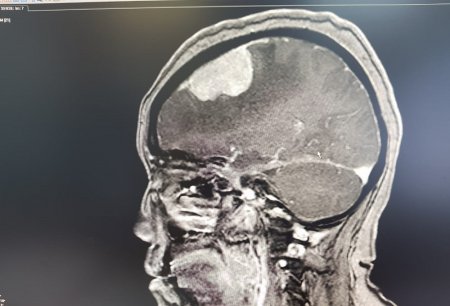

Опухоль мозга диаметром семь сантиметров удалили пенсионерке врачи Мангистау

Дополнительное обследование в аппарате компьютерной томографии (КТ) и магнитно-резонансной томографии (МРТ) показали у пенсионерки наличие отека правого полушария головного мозга.

- Врачи 28 февраля провели операцию по удалению опухоли в правой лобно-теменной области путем костно-пластической трепанации черепа пациентки. Операция прошла успешно, без осложнений, опухоль удалена полностью, - отметили в пресс-службе управления здравоохранения.